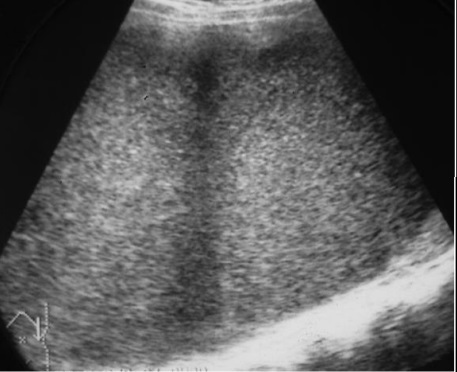

Echographie est la technique

de premiere de l'intention et de choix pour explorer

la splenomegalie . Par cela on peut en verifie la

diametre longitudinal de la rate , elle est grand et

voluminant quand la diametre lonitudinale depasse de

plus > 13cm . On peut en s'observe etat de la

parenchyme et des vaisseaux du hile de la rate |